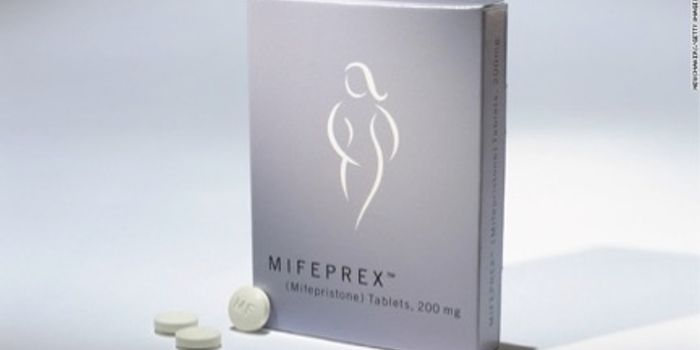

JAN 23, 2019Health & MedicineToday, women face a variety of challenging health issues, both physical and psychological which, in the past, have not r ...